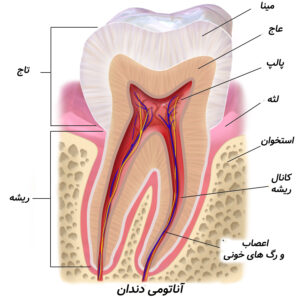

بسیاری از بیماران در مورد تفاوت کانال و ریشه دندان سردرگم هستند. در واقع، این دو مفهوم کاملاً متفاوتاند اما در زبان روزمره بهجای هم استفاده میشوند. به زبان ساده: ریشه دندان بخشی از ساختار فیزیکی دندان است که در استخوان فک قرار دارد و دندان را محکم نگه میدارد، در حالی که کانال ریشه یک فضای توخالی در داخل ریشه است که شامل پالپ، عصبها و رگهای خونی میشود. دانستن تفاوت کانال و ریشه دندان برای درک بهتر درمانهای دندانپزشکی مانند درمان ریشه یا روت کانال تراپی اهمیت زیادی دارد.

ریشه، بخشی از دندان است که زیر لثه قرار دارد و آن را به استخوان فک متصل میکند. هر دندان میتواند یک یا چند ریشه داشته باشد. سطح ریشه با مادهای به نام سیمان دندانی پوشیده شده و از طریق رباطهای پریودنتال به استخوان فک متصل میشود.

کانال ریشه (Root canal)

کانال ریشه دندان همان مجرای درون ریشه است که پالپ (عصب، بافت همبند و رگهای خونی) در آن قرار دارد. ساختار کانال ممکن است ساده یا بسیار پیچیده باشد. پیچیدگی آن نقش مهمی در موفقیت درمانهای اندودنتیک دارد.